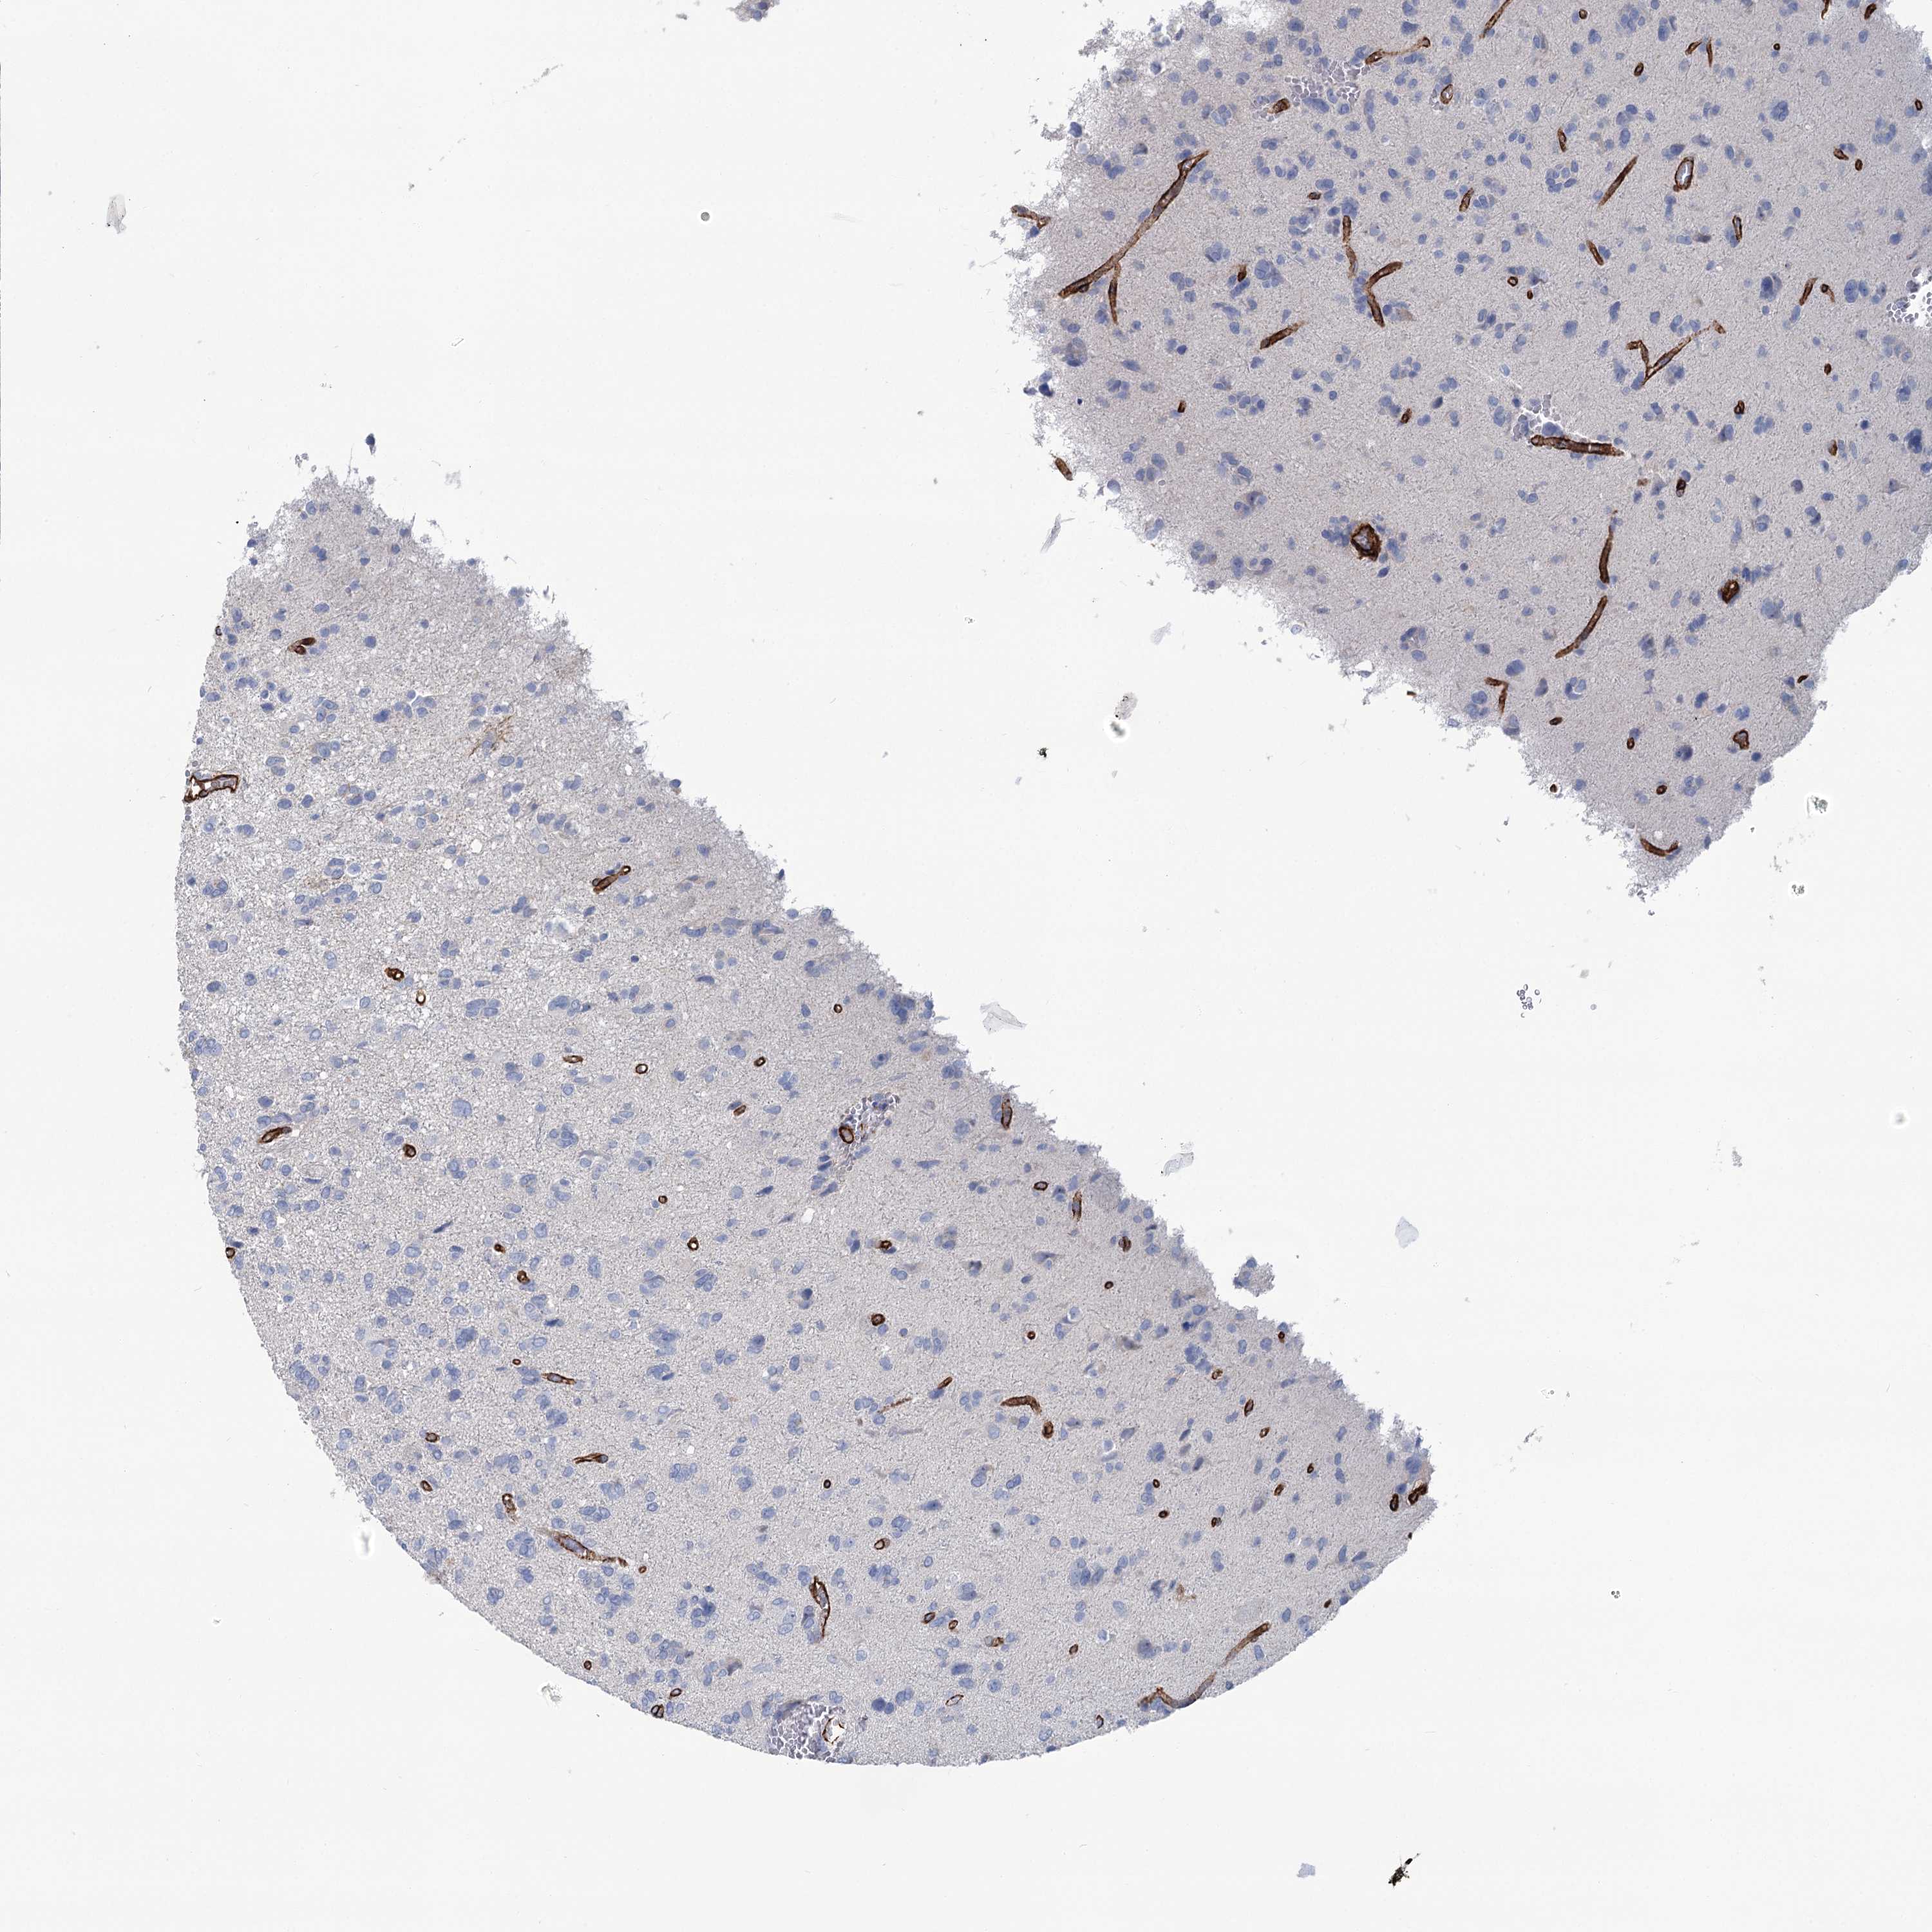

GLIOMA - Protein expressioni

A mouse-over function shows sample information and annotation data. Click on an image to view it in a full screen mode. Samples can be filtered based on level of antibody staining by selecting one or several of the following categories: high, medium, low and not detected. The assay and annotation is described here.

Note that samples used for immunohistochemistry by the Human Protein Atlas do not correspond to samples in the TCGA dataset.

Antibody stainingi

Antibody staining in the annotated cell types in the current human tissue is reported as not detected, low, medium, or high, based on conventional immunohistochemistry profiling in selected tissues. This score is based on the combination of the staining intensity and fraction of stained cells.

Each image is clickable and will lead to virtual microscopy that enables deeper exploration of all samples and also displays staining intensity scores, fraction scores and subcellular localization as well as patient and tissue information for each sample.

Antibody HPA038143

Antibody HPA038144

Staining

High

Medium

Low

Not detected

Intensity

Strong

Moderate

Weak

Negative

Quantity

>75%

75%-25%

<25%

None

Location

Nuclear

Cytoplasmic/membranous

Cytoplasmic/membranous,nuclear

Glioma, malignant, High grade

Glioma, malignant, Low grade

Glioblastoma, NOS